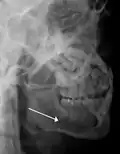

lateral oblique image demonstrating a fractured mandible.

Towne's view of a bilateral condyle fracture. White arrow is a fracture on the neck of the condyle. Black arrow shows the condyle pulled to the medial. The same injury can be seen on the opposite side -